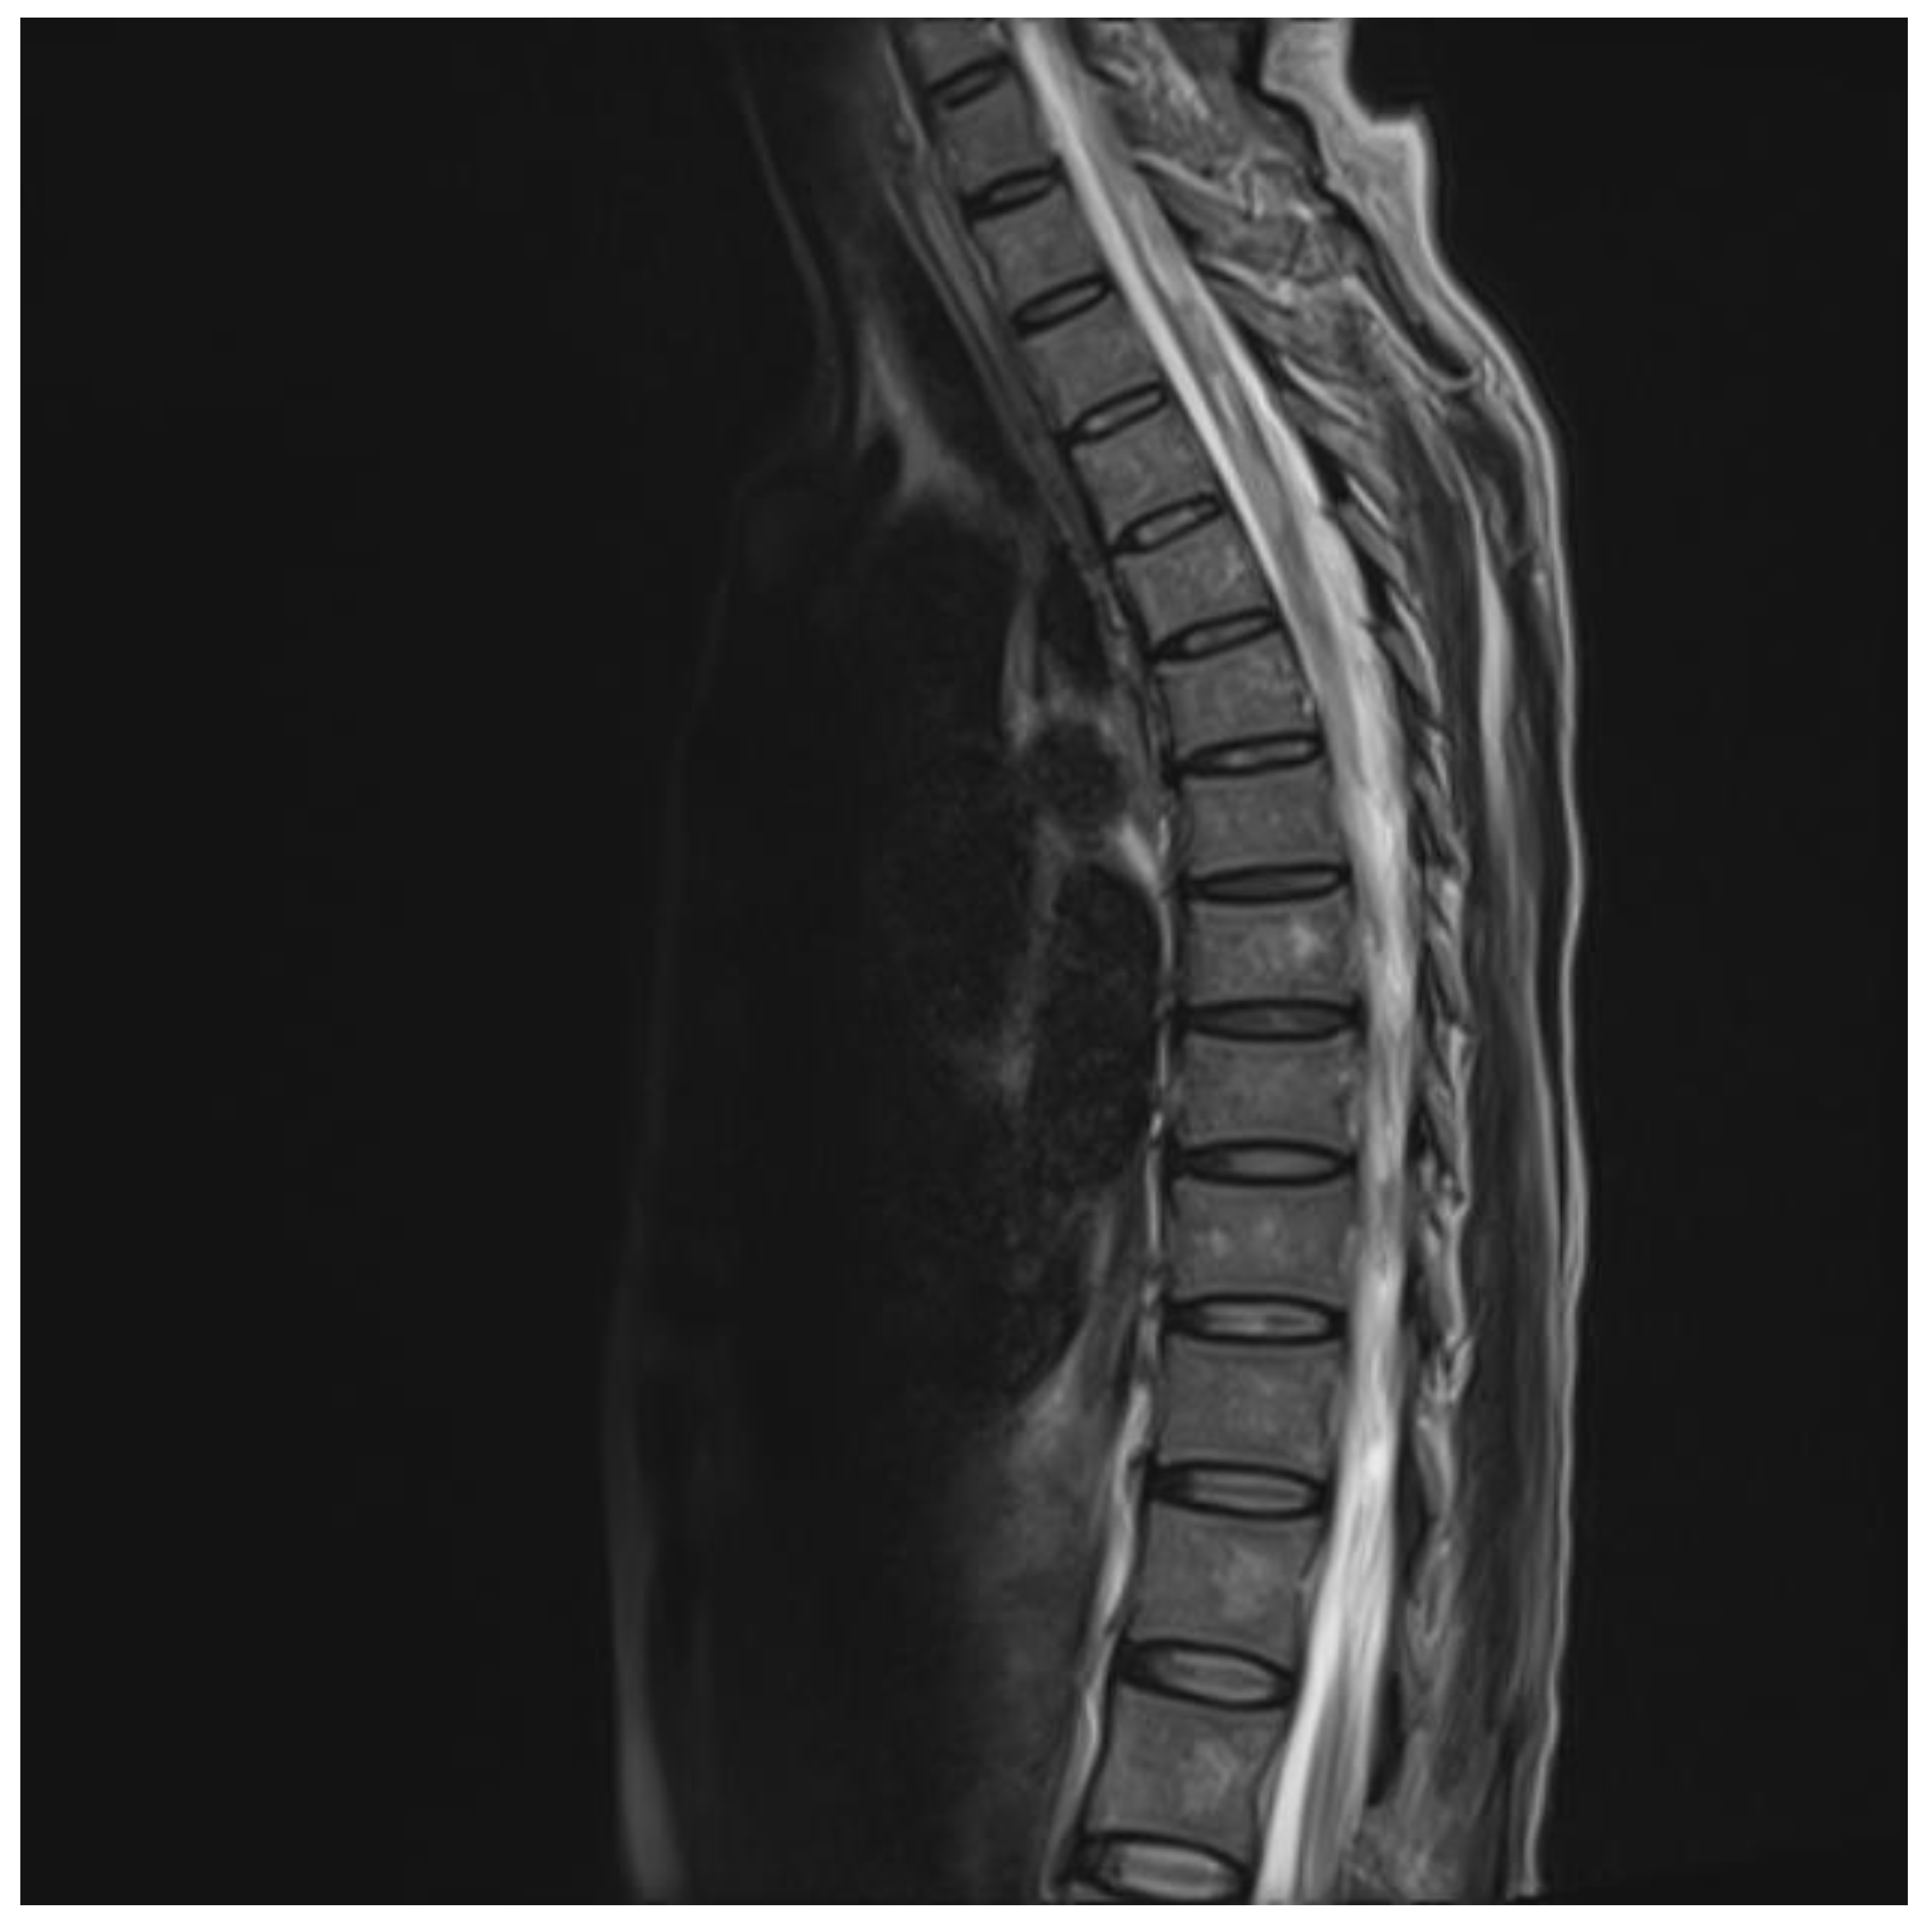

The chest and brain tomography did not display any abnormalities. The spinal MRI performed on the second day of hospital admission showed irregular intramedullary signal enhancement on the T2 sequence with diffuse lesions ranging from the sixth cervical vertebra to the seventh dorsal vertebral (Figure 1). The T1 sequence showed the spinal cord with multiple hypointense lesions centrally located at the cervical–dorsal level (Figure 2), while the transversal image T2-weighted image of the spinal cord showed hyperintense lesions in the white matter and in the posterior portion of the spinal cord (Figure 3).

Figure 1.

T2 image showing hyperintensity of the central portion of the cervical and thoracic cord.

MRI has an important role in the diagnosis and classification of TM, as it allows us to identify hyperintense spinal cord injury in T2-weighted images, and when it affects at least three vertebral segments in the sagittal slices, TM is classified as LETM [3]. T2- weighted MRI demonstrated an intramedullary increased signal in the central portion of the spinal cord as the most common finding [5]. MRI images in immunocompetent patients with TM show that the cervicothoracic cord is affected more frequently, as in our case, unlike immunosuppressed patients, in which tropism has been seen in the cauda equina or the conus medullaris [13]. The aforementioned findings coincide with the RMI in the case report presented, in which hyperintense cervicothoracic spinal cord involvement was observed in the T2-weighted image. This was specifically seen in patients with NMO (anti-AQP4 Ab) associated with patients with SLE and Sjögren’s disease [3,14]; while there is evidence of markedly hyperintense foci on T2 described as “Bright Spotty Lesions”, characteristic for NMO, in this case, anti-AQP4 antibody sera were not performed. However, the results of the IgM serological test for cytomegalovirus was positive, which confirmed the acute installation of the infectious image.